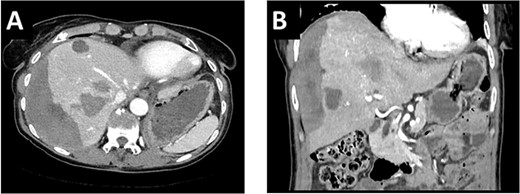

During ALPPS step 1, the right accessory artery was clearly identified. Intraoperative ultrasound revealed five metastases on the left side, which were all removed by atypical resections (Fig. 4A). Since the biopsy-induced liver hematoma on the right side was intrahepatic, hematoma evacuation was avoided during ALPPS step 1 due to the potential risk of liver injury or mobilization-associated bleeding. In the follow-up volumetry 6 days after ALPPS step 1, the sFLR increased from 30 to 59%. Liver function tests after step 1 showed sufficient hepatic function (LiMAx 326 mcg/kg/h and ICG R15 2.7%). Therefore, ALPPS step 2 including evacuation of the perihepatic hematoma and completion right hemihepatectomy was performed 7 days after step 1 (Fig. 4B). In the postoperative course, there were no signs of liver failure. However, the patient developed a wound infection (Clavien-Dindo grade II), which was managed by bedside vacuum-assisted closure therapy. The patient was discharged on postoperative day 10 following ALPPS step 2 surgery. Adjuvant chemotherapy with FOLFOX for 3 months was recommended. The primary tumor in the sigmoid colon regressed during chemotherapy and robotic-assisted left hemicolectomy was performed 6 months after the ALPPS procedure. At last follow-up, 15 months after ALPPS there were no signs of tumor recurrence.

(A). Left hemiliver after cleaning of the FLR with five atypical liver resections. (B) Remaining left hemiliver after completion right hemihepatectomy during ALPPS step 2.